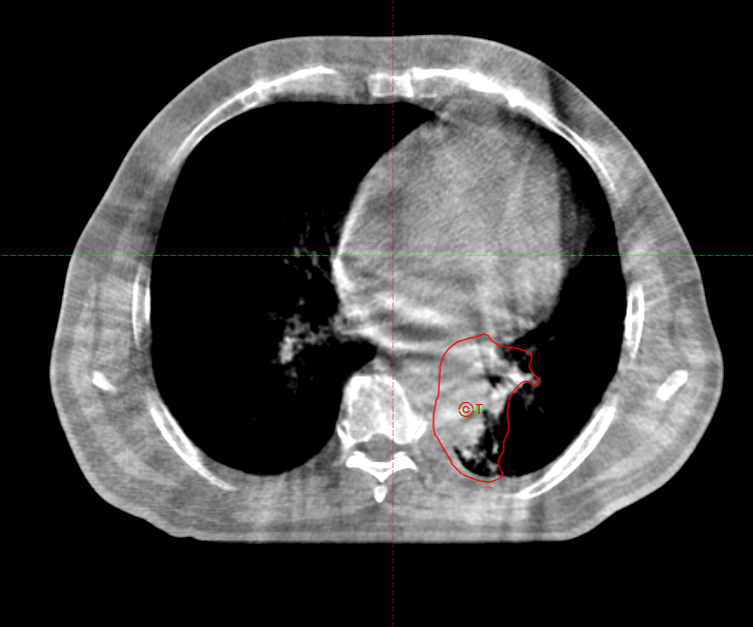

Заключение ПЭТ-КТ с ФДГ от 29.03.2022г:

- картина центральной опухоли левого легкого с признаками обструктивного пневмонита, мтс с поражением ипсилатеральных и подкаринальных лимфоузлов.

В воротах левого легкого определяется метаболически активный опухолевый узел с вовлечением главного, нижнедолевого, частично верхнедолевого бронхов, общими наибольшим размерами около 83 мм в аксиальной проекции и до 81 мм в краниокаудальной проекции, SUVmax=21.41. Опухоль располагается на расстоянии около 30 мм от киля трахеи с вовлечением левой легочной артерии (обхват около 50%) и тесным прилеганием к нисходящей аорте. Окружающая паренхима левого легкого с признаками воспаления. В правом легком очаговая и инфильтративная патология легких не определяется.Определяются метаболически активные медиастинальные лимфоузлы, наибольшими размерами/накоплением РФП: подкаринальной группы (7) до 10 мм, SUVmax=7.49; субаортальной группы (5) до 8 мм, SUVmax=4.70. Лимфоузлы ворот левого легкого четко не дифференцируются, вероятнее сливаются с основной опухолевой массой.

В воротах левого легкого определяется метаболически активный опухолевый узел с вовлечением главного, нижнедолевого, частично верхнедолевого бронхов, общими наибольшим размерами около 83 мм в аксиальной проекции и до 81 мм в краниокаудальной проекции, SUVmax=21.41. Опухоль располагается на расстоянии около 30 мм от киля трахеи с вовлечением левой легочной артерии (обхват около 50%) и тесным прилеганием к нисходящей аорте. Окружающая паренхима левого легкого с признаками воспаления. В правом легком очаговая и инфильтративная патология легких не определяется.Определяются метаболически активные медиастинальные лимфоузлы, наибольшими размерами/накоплением РФП: подкаринальной группы (7) до 10 мм, SUVmax=7.49; субаортальной группы (5) до 8 мм, SUVmax=4.70. Лимфоузлы ворот левого легкого четко не дифференцируются, вероятнее сливаются с основной опухолевой массой.